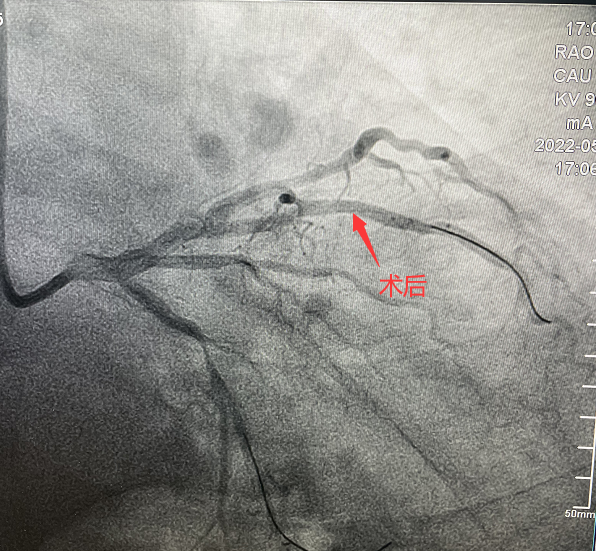

患者,51歲,男性,入院診斷為:冠心病、不穩(wěn)定型心絞痛。冠狀動脈造影顯示對角支90%狹窄病變。對于該類患者,通過介入治療(PCI)方式早期干預(yù)相關(guān)血管可明顯減輕患者癥狀,減少死亡率、并發(fā)癥,改善患者的預(yù)后。在醫(yī)生與患者及家屬溝通時,患者家屬提到,他們了解得知臨床有一種新型的可吸收支架,置入體內(nèi)后能完全被降解和吸收,患者及家屬希望能用這種新型的支架進(jìn)行手術(shù)治療。由于生物可吸收支架有著嚴(yán)格的適應(yīng)癥,因此經(jīng)過嚴(yán)格評估,最終對患者進(jìn)行了Xinsorb生物可吸收支架(BRS)置入術(shù)。支架植入術(shù)后,經(jīng)IVUS檢查,支架貼壁良好,結(jié)果完美,手術(shù)順利結(jié)束。

手術(shù)造影圖